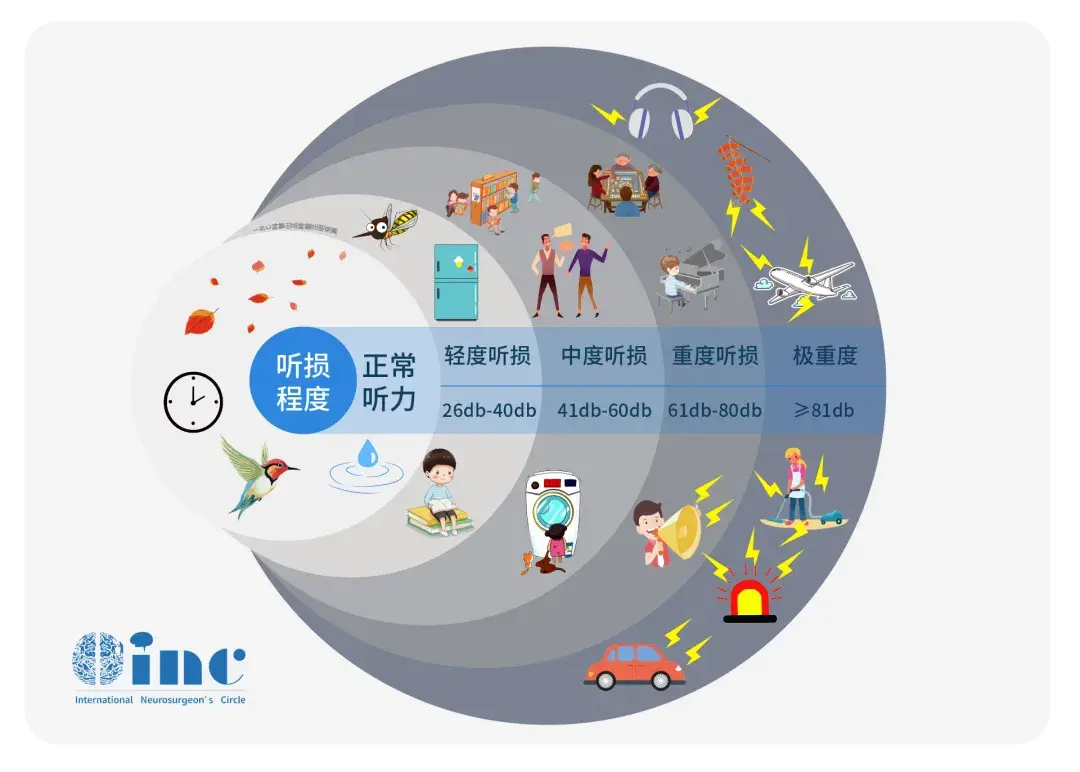

36岁的伊文,有20年左侧听力丧失病史,在过去一年中急性加重。她在喝水时也会出现呛咳,没有出现前庭症状、运动问题或任何其他症状。 检查时,她左侧听力显著丧失,但其他神经系统检查...